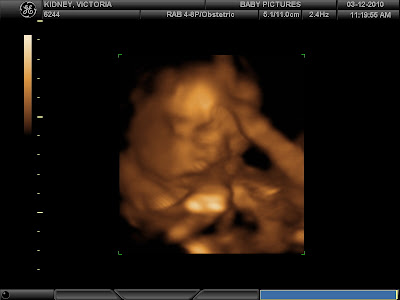

There's a preview of her little Chopita face. It's blurry and you have to try and look through it kinda like one of those 3D posters to see it, but there she is. The disfigurement looking thing between her eyes is actually placenta (or maybe just uterine wall, I can't remember), and you can see how she is holding the cord to her mouth. Either she's quite the little snuggler or she has her momma's appetite.